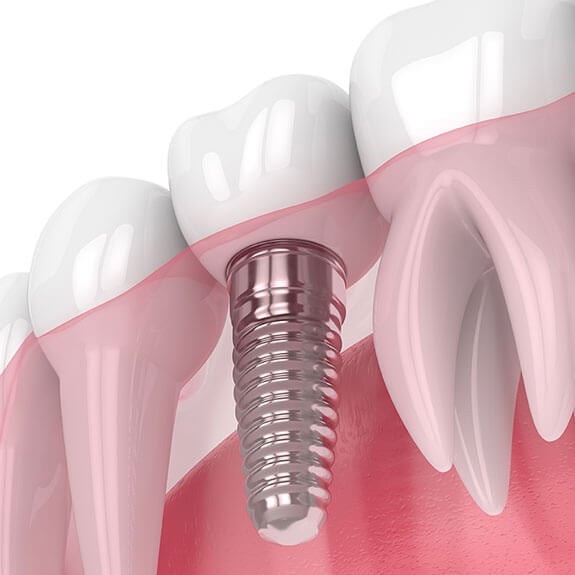

Dental implants are artificial tooth roots, typically made of biocompatible titanium, that are surgically placed into the jawbone. These implants serve as a sturdy foundation for replacement teeth, ensuring a natural fit and function. Unlike traditional dentures, implants integrate with the bone, preventing bone loss and preserving facial structure.

Implant Placement – A titanium post is surgically inserted into the jawbone, where it gradually fuses with the bone in a process called osseointegration.

Abutment Placement – A small connector is attached to the implant, serving as a base for the new tooth.

Crown Attachment – A custom-made crown is fixed onto the abutment, completing the restoration for a natural-looking smile.